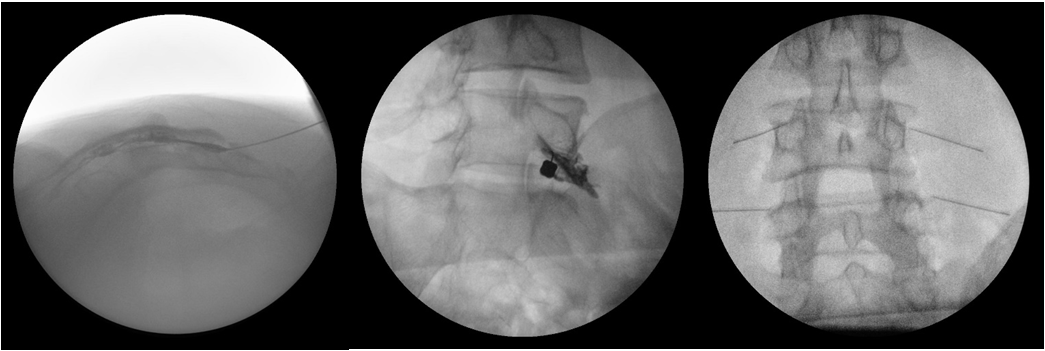

C-arm 유도 주사치료

• 척추와 관절 주위 구조물을 C-arm으로 확인하며 정확하고 안전하게 치료 부위에 약물을 주입할 수 있습니다.